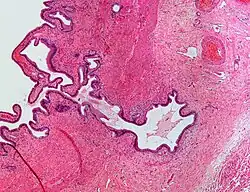

Micrograph showing Rokitansky–Aschoff sinus. H&E stain.

Rokitansky–Aschoff sinuses are pseudodiverticula or pockets in the wall of the gallbladder. They may be microscopic or macroscopic. Histologically, they are outpouchings of gallbladder mucosa into the gallbladder muscle layer and subserosal tissue as a result of hyperplasia and herniation of epithelial cells through the fibromuscular layer of the gallbladder wall.[4]